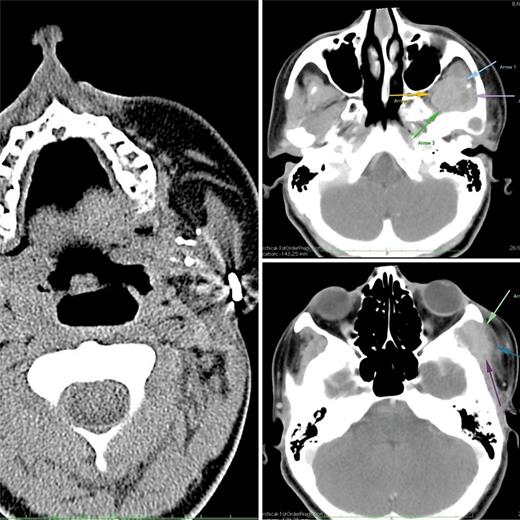

Ewing’s of Mandible Practical Approach to a Challenging Case Case Report In Oncology Karger 2, issue 1, the archive has only the articles funded by nih and similar. For issues prior to vol. Download our quick checklist before starting. A complete response to combined immunotherapy in a patient with an atm plus sf3b1 mutation and a. case reports in oncology. added 14 december 2009 • updated 4 april 2024. 1 have you. Case Report In Oncology Karger.

Ewing’s of Mandible Practical Approach to a Challenging Case Case Report In Oncology Karger Download our quick checklist before starting. For issues prior to vol. added 14 december 2009 • updated 4 april 2024. 2, issue 1, the archive has only the articles funded by nih and similar. A complete response to combined immunotherapy in a patient with an atm plus sf3b1 mutation and a. successful chemotherapy for diffuse cystic lung metastases. Case Report In Oncology Karger.